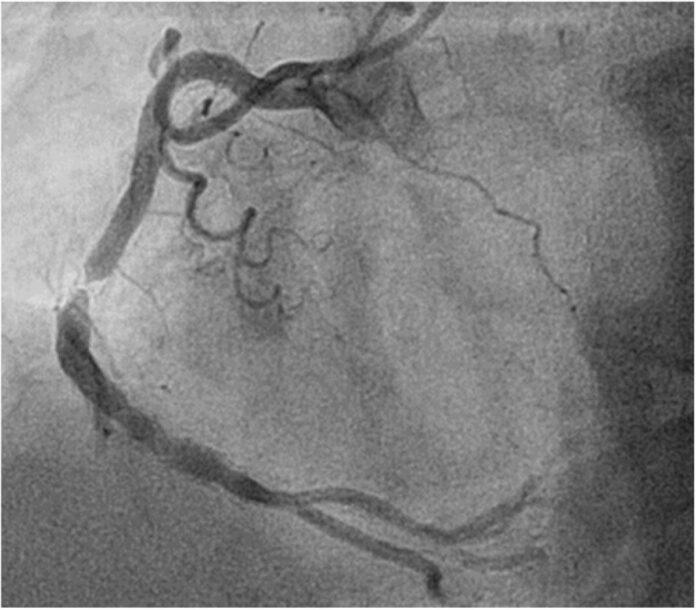

心血管疾病長年位居國人十大死因,其中冠狀動脈疾病是心肌梗塞與猝死的主因。透過心導管手術置入心臟支架,能有效打通阻塞血管,恢復心臟供血。然而,這並非一勞永逸,術後仍存在一個潛在風險—支架再阻塞。

支架再阻塞指血管在置入支架後數月至數年內再次狹窄。主要原因包括,血管內皮細胞過度增生,使支架內膜變厚、動脈硬化進一步惡化,及不良生活習慣如抽菸、血糖控制不佳等,導致血管再次受損。儘管新一代**藥物塗層支架(DES)**已大幅降低再狹窄率(5-10%),但此風險仍不容輕忽。

除了藥物支架,近年來也發展出「可吸收性支架」與「新一代藥物球囊」等新技術,目標是進一步降低再阻塞風險,並實現血管的「無痕治療」。廖振宇強調,心臟支架是救命的橋樑,但健康的生活方式才是長遠的道路。患者與家屬不應僅依賴手術,而是從日常做起,才能真正遠離心血管疾病的威脅。